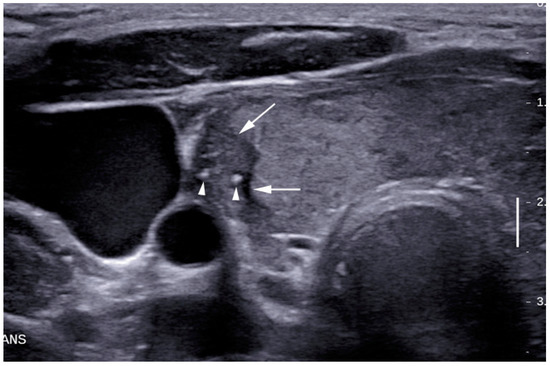

| Yes | 6 (7.1%) | 21 (77.8%) | <0.05 |

| No | 78 (92.9%) | 6 (22.2%) | (0.12–0.49) |